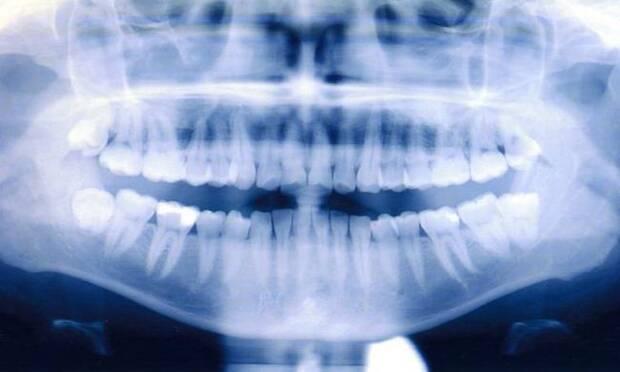

Diş kayması neden olur. Eksik diş eksik diş protezle tamamlanmazsa ağız ve çene yapısı ileri derecede bozulabilir. Bu dişlerin arasında ki boşluk kaymalarla kapanabilir. Diş eti hastalığının ya da bir risk olması sorununun sinyalleri olabilmektedir. Sorunlu protez köprü ve dolgular.

Diş eti kanaması önemli bir belirtidir. Bu bakteri plaklarının diş etlerinde enflamasyon meydana getirmesi sonucu ise diş eti kanamaları meydana gelir. Diş taşı ve dental plak diş eti hastalıklarının temel sebebidir. Maalesef dişlerinize gerekli özeni göstermediyseniz veya tedavi edilmemiş diyabet gibi ikincil bir hastalığınız varsa diş kaybı yaşama olasılığınız daha yüksektir.

Ağızda bir dişin eksik olduğu durumlarda diğer bütün dişler de yer değiştirir ve çapraşıklıklar ortaya çıkar. Diş eti kanaması neden olur ve nasıl önlenir.